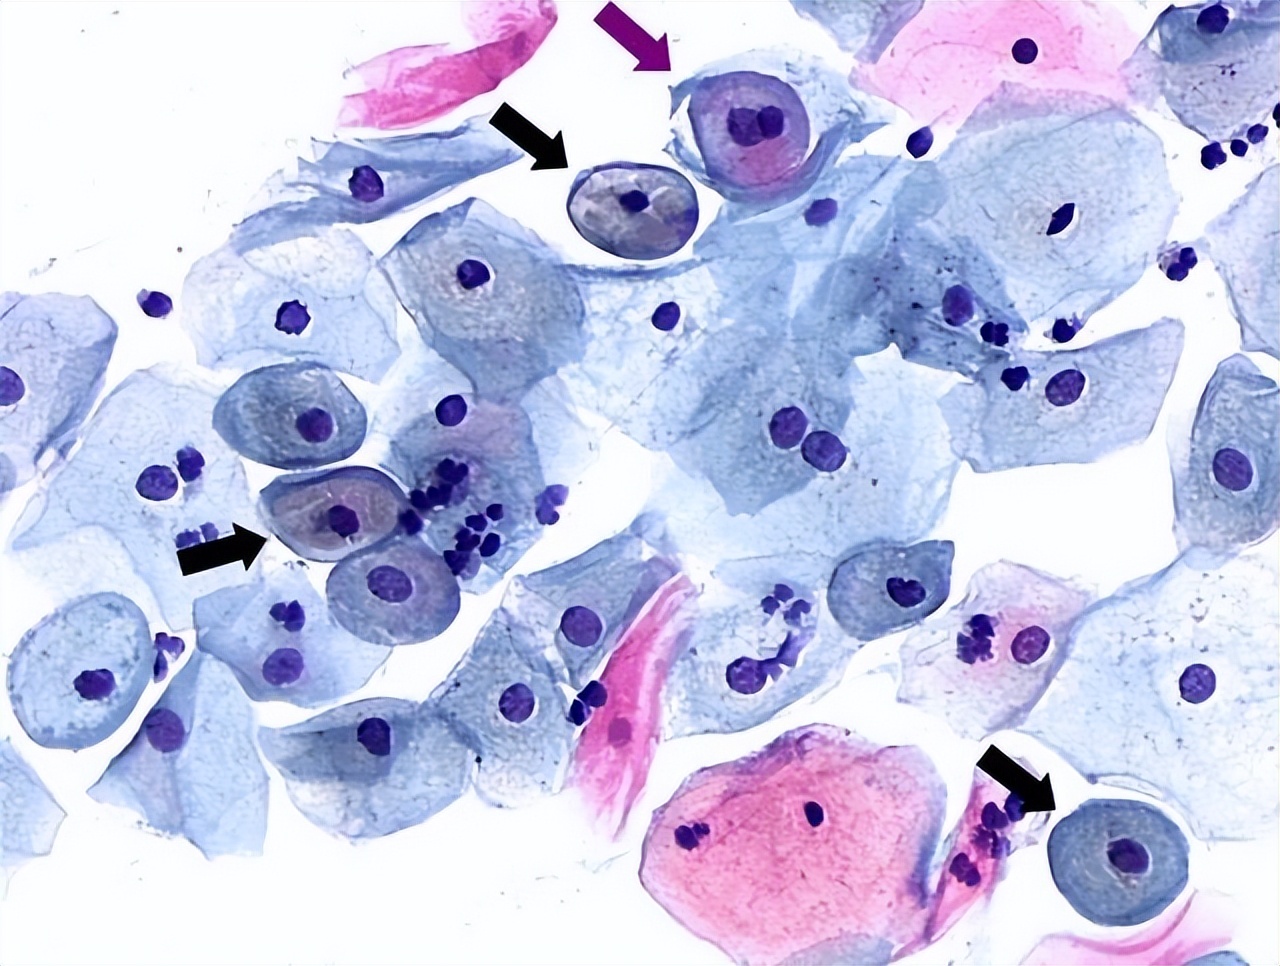

TCT炎症轻度指TCT检查结果提示轻度炎症,说明宫颈存在轻度炎症。此时病情相对较轻,并不存在恶性病变。TCT检查是通过显微镜电子扫描及时发现宫颈脱落细胞中的异常细胞,这些细胞中可存在炎性细胞或肿瘤细胞,需通过TCT检查结果进行分层管理。当提示为炎症轻度时,说明只是有轻度炎症,未出现宫颈癌的恶性细胞,无需过多担心,但应重视治疗,防止病情加重。